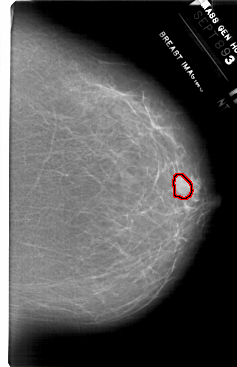

FILE: A_1717_1.RIGHT_CC.OVERLAY

TOTAL_ABNORMALITIES 1

ABNORMALITY 1

LESION_TYPE MASS SHAPE LOBULATED MARGINS ILL_DEFINED

ASSESSMENT 4

SUBTLETY 3

PATHOLOGY BENIGN

TOTAL_OUTLINES 1

BOUNDARY